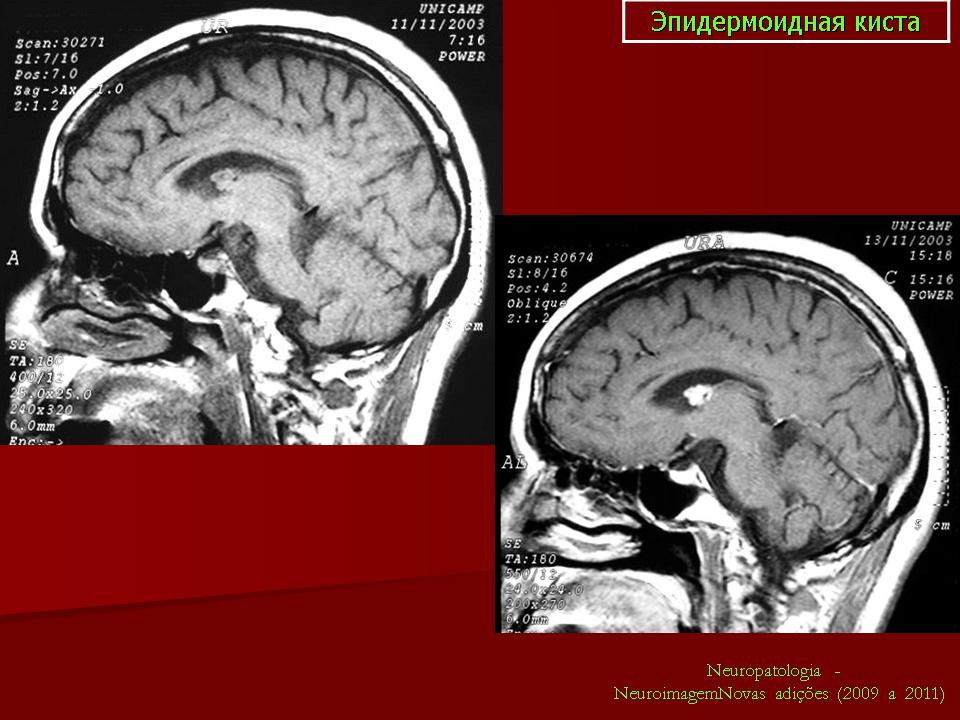

Эпидермоидная киста

Эпидермоидная киста.